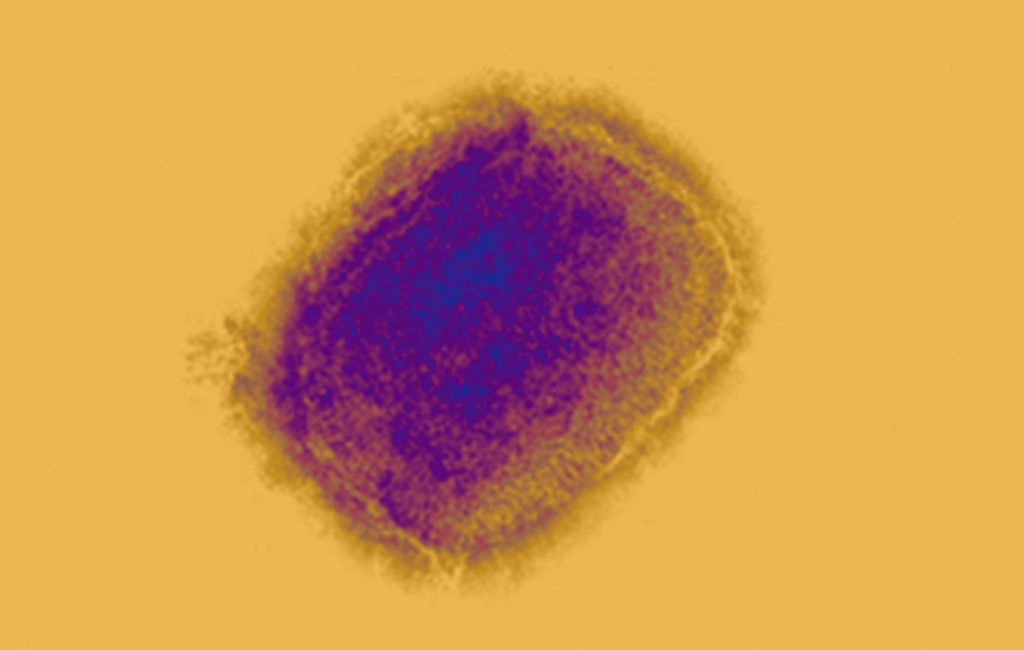

Virus verola mico

Imatge del virus de la verola del mico, que es pot transmetre dels animals als éssers humans. (ECDC)